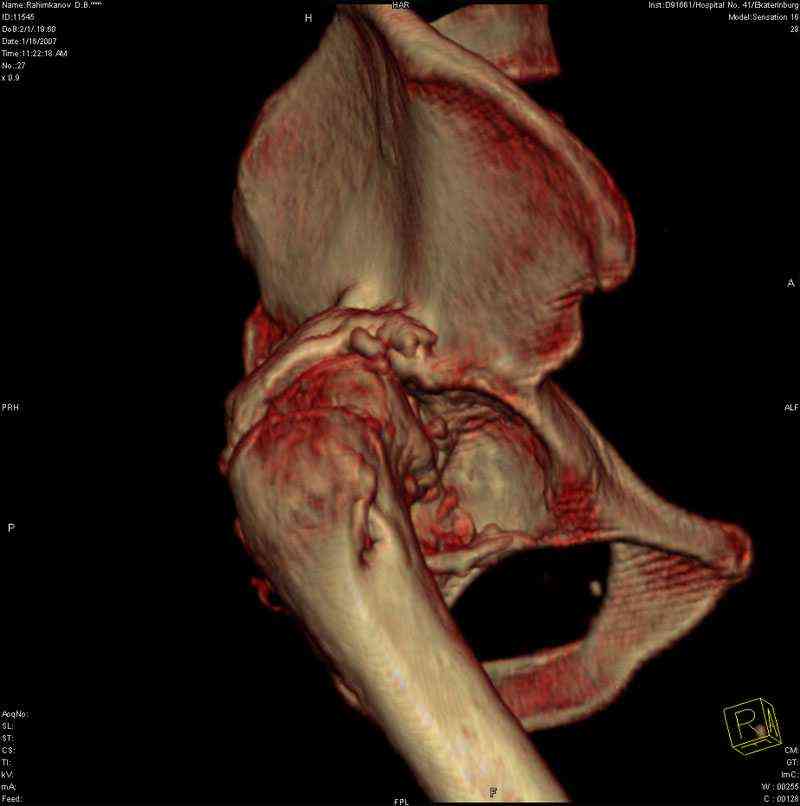

К нам обратился житель Казахстана с застарелым вывихом бедра. Травма год назад, вместо синтеза заднего края казахскими умельцами установлена клинковая пластина, через 6 мес удалена. Больной ходит с тростью,сгибание в т-б 90, разгибание 170, укорочение 5 см, боли не выражены, анальгетиками не пользуется. Настроен на эндопротезирование в клинике, где есть опыт подобных операций (возможно за рубежом).Наш план: аппарат таз-бедро, постепенное низведение бедра, "октопус" с пластикой. Но с такими большими дефектами мы не сталкивались.Есть вариант сначала аппарат, затем реконструкция впадины, протез обычный через 4-6 мес.Есть мнение не восстанавливать длину. Будем признательны за полезные советы. Было бы интересно посмотреть пример.

Кстати, судя по рентгенограммам и КТ истинная разница в длине ног не столь велика, укорочение, главным образом, за счет контрактур.